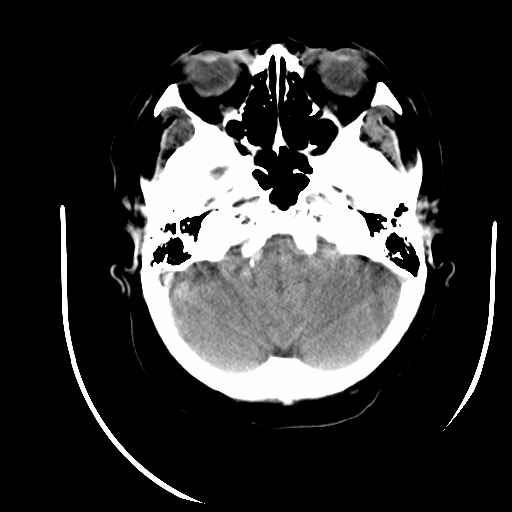

标题: CT16645:F70Y,头晕,头昬呕吐1天入院,右下肢肌力肌张力减底 [打印本页]

女70 头晕,头昬呕吐1天入院,右下肢肌力肌张力减底。高血压bp180/100

临床诊断:脑血管病1脑出血2脑梗塞

左侧内囊腔梗,脑底动脉硬化,多发钙斑形成,脑干梗塞可疑,空泡蝶鞍可疑

考虑左侧小脑梗塞。脑底动脉硬化

可疑脑干区腔梗,脑底多发动脉粥样硬化。

1)右侧额叶深部腔隙性脑梗塞。2)椎基底动脉迂曲、钙化。

右放射冠陈旧梗塞

椎基底动脉迂曲、钙化。右侧额叶腔隙性脑梗。